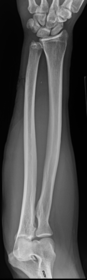

| AP Forearm | not AP - wrist is internally rotated, proximal radius and ulna are superimposed |

| Lateral Forearm | Elbow is not 90 degrees proximal radius and ulna are superimposed |

| AP Forearm | ANATOMY: entire forearm: wrist joint -> elbow joint CRITERIA: slight superimposition of proximal radius/ulna POSITIONING: CR perpendicular @ midforearm |

| Lateral Forearm | ANATOMY: entire forearm including wrist joint and elbow joint CRITERIA: humeral epicondyles must be superimposed distal radius/ulna superimposed half of radial head superimposed by coronoid process olecranon process in profile POSITIONING: CR perpendicular @ midforearm |